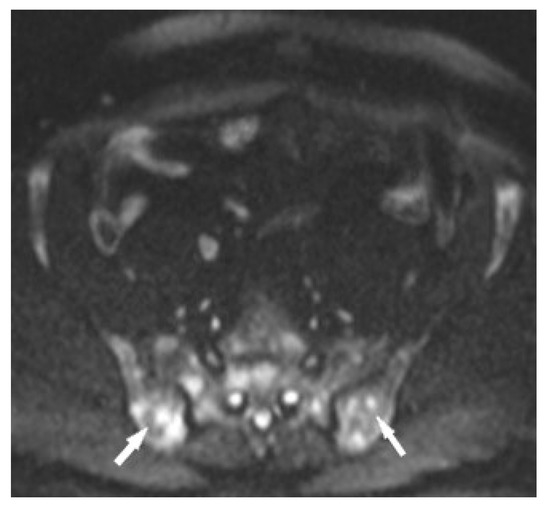

MR is a highly sensitive imaging modality that can detect bone marrow involvement in sarcoidosis. It also provides the detailed information on soft tissue involvement, synovitis and joint inflammation. Occasionally, MR images detect clinically and radiologically silent lesions (Figure 3a,b).

Figure 3. Radiograph (a) and magnetic resonance of the shoulder joint. T1-weighted image with fat saturation and with contrast administration (b). 40-year-old patient with sarcoidosis. Two contrast-enhanced lesions in the acetabulum of the joint ((b), asterisk) not visible on X-ray (a).